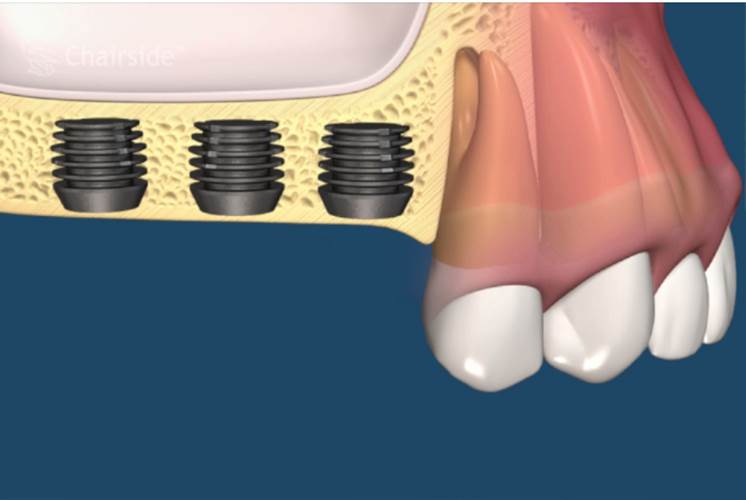

• 手術階段

第一期植體植入:精確測量可供植牙的牙孔,並植入鈦合金的人工牙根然後縫合,在手術後7天拆線。(2-3個月追蹤傷口複檢一次)一般植入的人工牙根需4-6個月才和骨頭結合。手術後72小時內,傷口若出現腫脹,在手術後24小時內可用冰敷來減輕腫脹情況,手術後的復原時期,需特別的清潔照顧。第二期植牙接出手術:經4-6個月骨整合後,進行第二次植體接出手術。

植體接出後,給予臨時假牙試戴,進行調整咬合與美觀部位的修飾,待病人適應一段時間後,依據調整好的咬合狀態進行印模製作永久假牙。(圖01-03)

圖01

圖02

圖03